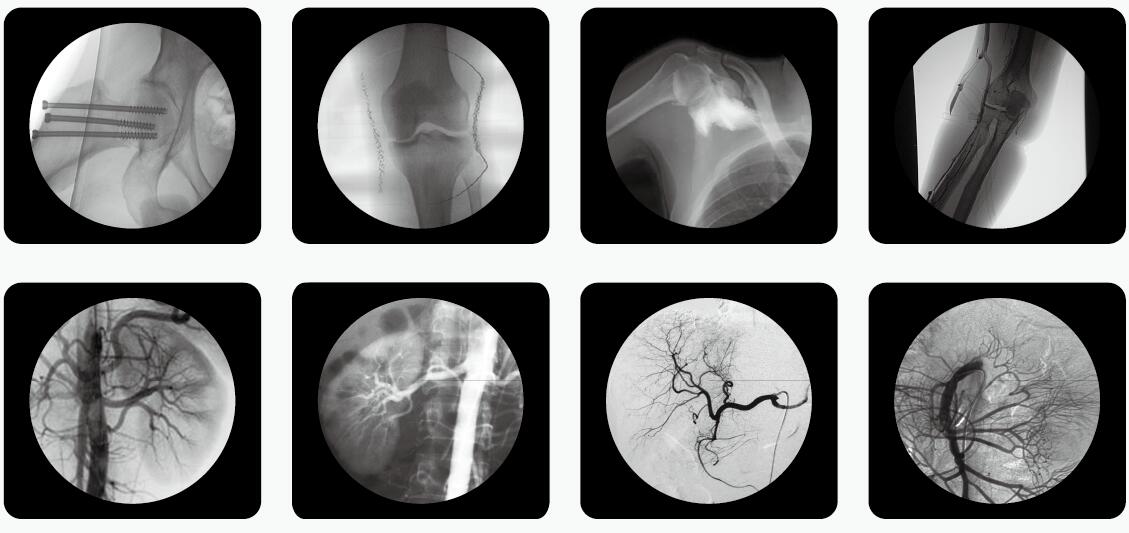

如何在滿足影像診療質(zhì)量的同時,有效地控制輻射危害,已成為放射學發(fā)展中的一個亟待解決的重要問題。C臂透視機是骨科手術中使用較多的一款放射性醫(yī)療設備。

C臂透視機

骨科醫(yī)生用C臂機透視比較多,如何在手術過程中實施安全防護措施,極大限度地減少電離輻射對人體的危害,顯得尤為重要,以下是小編為大家整理了C臂透視機防護三大原則,來和大家一起分享。